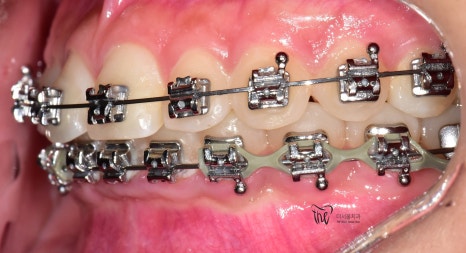

이 분은, 교정장치를 달고 있는 상태로 오셨는데

따라야 되는데 교합면 사진을 보게 되면

뭔가 전체 치열 자체는 고르게 느껴지죠?

근데, 이거 다 끝난게 아닙니다.

아직, 치아 얼라이먼트가 완성이 되지 않았습니다.

치아 얼라이먼트라는 것은 치열이 U 자 형태로

둥글게 악궁을 형성하고 있어야 되는데 살짝살짝

군데군데 아쉬운 점이 남아있습니다.

그러면서, 치아 레벨링이 완성이 되질 않았습니다.

레벨링 이라는 것은 위, 아래 치아들을 동시에

놓고 봤을 때의 가지런함을 뜻합니다.

여러모로.. 아쉬운점이 많았으나

치료 기간 2021.01.03 ~ 2022.08.14